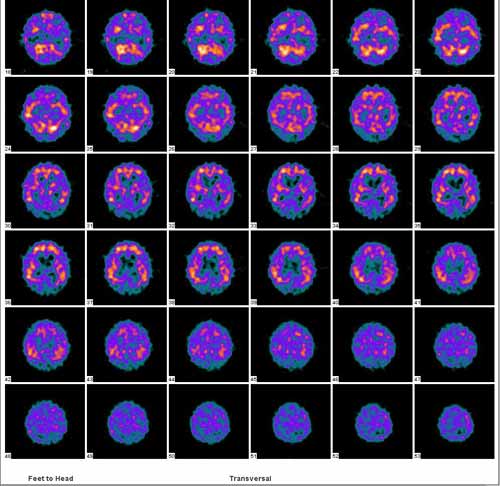

射性弥漫性减低,显影模糊不清,结构紊乱,但双侧基本对称;   双侧基底节、丘脑、小脑放射性弥漫性严重减低,与颌面及颈部本底显影无法区分。   检查结论:大脑血流灌注弥漫性严重减